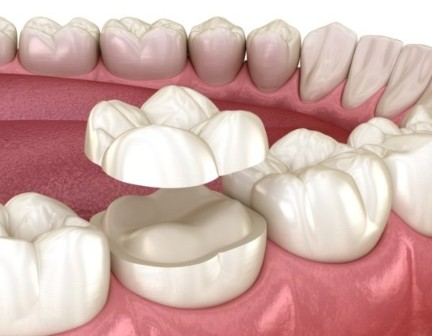

덮어 씌우는 크라운은

단단하게 보호해 주는 역할을 하지만,

많은 양의 삭제와 신경치료가

필요할 수도 있어서 부담이 될 수 있습니다.

그래서 여기서 오버레이란

크라운처럼 전체를

덮지 않고 손상된 부위만

덮어주는 방식을 말합니다.

비교적 치아 삭제량이 적고,

자연치아를 보존할 수 잇다는

장점이 있습니다.